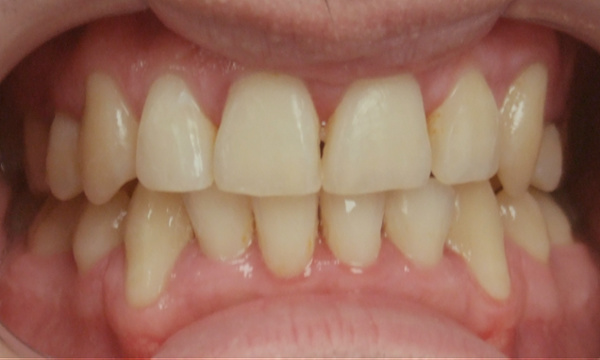

Not all orthodontic journeys start on the right path. This patient came to us with partial braces and a desire for clinical excellence. Dr. Martinez accepted the challenge, providing the expert, hands-on care necessary to "rescue" this complex case. After 24 months of specialized treatment in our Miami orthodontic practice, we achieved a healthy, stable, and properly aligned smile. Experience the difference 35 years of expertise makes.